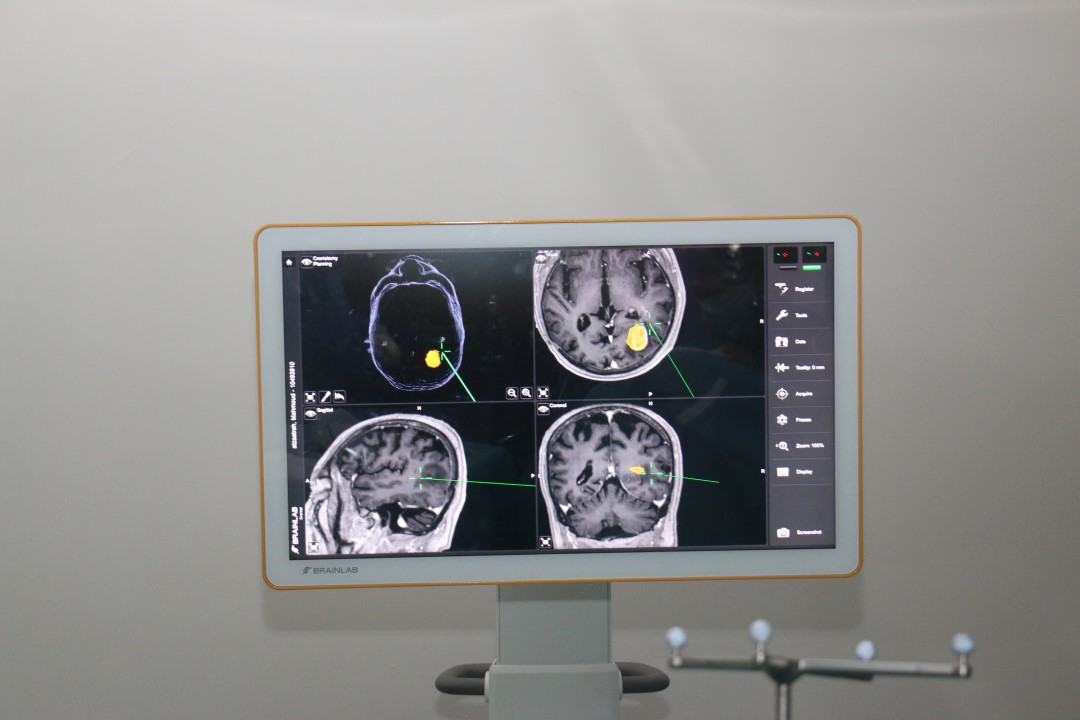

قام استشاري جراحة أورام الدماغ الدكتور ماهر عليان في المستشفى التخصصي ولأول مرة في القطاع الخاص بالأردن استئصال ورم دبقي في الدماغ باستخدام جهاز الملاحة ومادة 5- ALA Gliolan .

ويستخدم جهاز الملاحة للمرضى الذين يعانون من الاصابة بالأورام الواقعة في أماكن حرجة من الدماغ، والتي تتطلب دقة متناهية في تحديد مكان الورم.